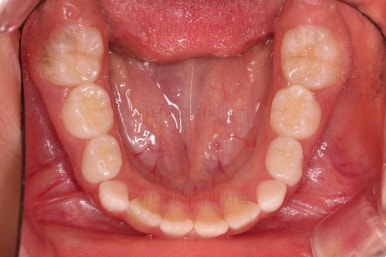

1. 초진

부산어린이교정 키다리아저씨치과에 처음 내원했을 당시의 입안의 모습입니다.

앞니가 거꾸로 물리는 전형적인 앵글씨 3급 부정교합 환아의 모습이었습니다.

아직 유치가 많이 남아 있었꼬, 아래 앞니는 4개가 영구치 맹출, 윗니는 2개가 영구치 맹출 상태였습니다.